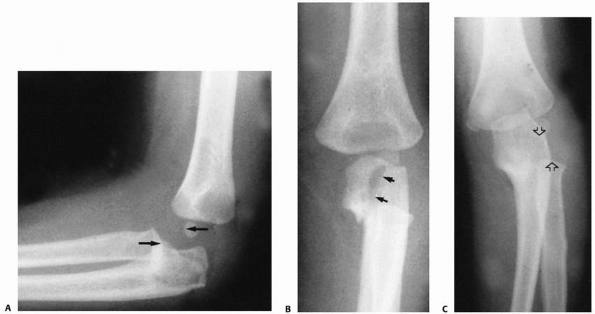

![]() |

FIGURE 12-25 Type II Monteggia fracture-dislocation. The typical radiographic findings include (A) a posterior dislocation of the radial head (arrows) and (B) a proximal metaphyseal fracture, which may extend into the olecranon (arrows). The radial head also may be posterolateral (arrows) (C).

the pertinent features for classifying this fracture. The typical

extension into the olecranon (Fig. 12-25).37,91,135 Midshaft fractures also occur, with an oblique fracture pattern.8,37,91 The radial head is dislocated posteriorly or posterolaterally9

fractures of the anterior margin of the radial head have been noted.37,97 Initially,

these are subtle in children but can lead to progressive subluxation and make late reconstruction difficult (Fig. 12-26).